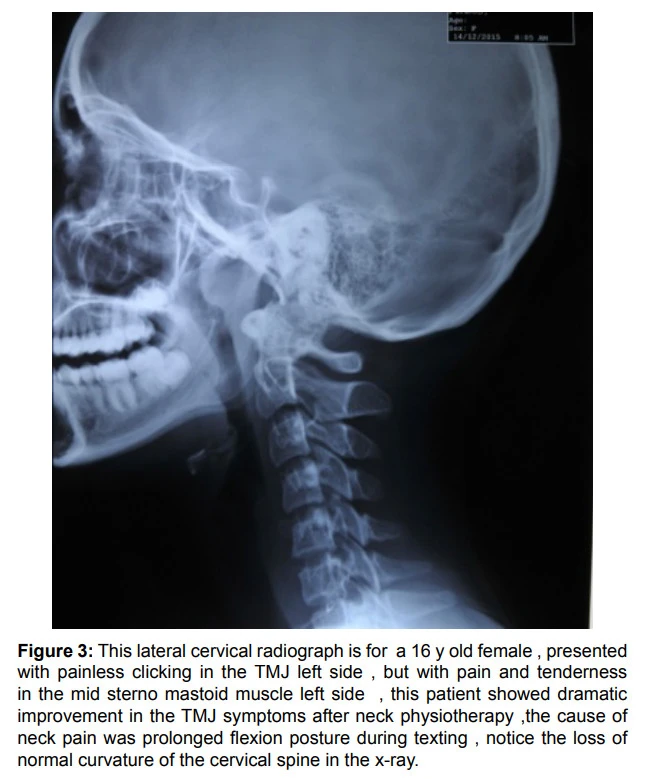

위 사진은 왼쪽 턱관절잡음이 들리던 16세 여성의 목통증이 목치료를 받고 턱관절 증상도 개선된 사례를 소개한 것입니다. 그 이유는 경추의 정상적인 각도가 무너지면서 턱관절에 영향을 주기 때문으로 해석했는데요. 그만큼 경추의 노말 커브가 무너질수록 턱관절에는 더 큰 부담이 가게 됩니다.

그림출처: Aloosi, Suha N., et al. "Contribution of cervical spine in temporomandibular joint disorders: A cross-sectional study." J Interdiscipl Med Dent Sci 4.204 (2016): 2.